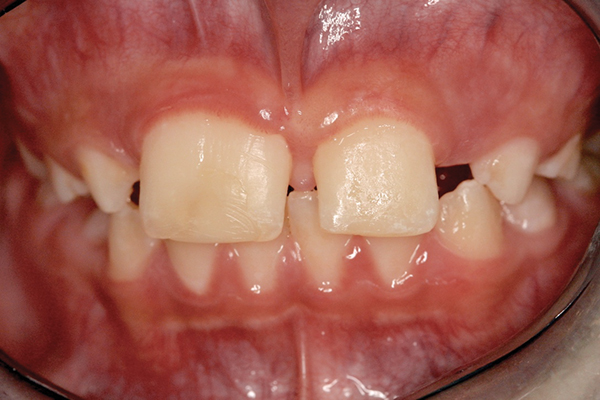

Fig 1 and Fig 2. Pretreatment photographs. Patient at 9 years of age on presentation.

A 9-year-old girl, referred to a prosthodontic office by her pediatric dentist, presented with her mother’s chief complaint: “The kids are teasing her about her big front tooth.” Findings from radiographic and clinical examinations revealed fused maxillary central-peg lateral incisors, teeth Nos. 7 and 8, and a congenitally missing lateral incisor, tooth No. 10 (Figure 1 through Figure 3). An implant was selected as the ideal treatment to replace tooth No. 10 when somatic growth was complete. A diagnostic wax-up was fabricated to determine if the fused tooth could be made to resemble two teeth, using pink composite to give the illusion of an interproximal papilla. The patient was referred for an orthodontic consultation to plan for closure of the diastema between teeth Nos. 8 and 9 and achievement of proper alignment for implant No. 10. The patient was also referred to a periodontist for pretreatment assessment of the tooth No. 10 site. An endodontist was consulted should exposure of the large pulp occur during tooth preparation.